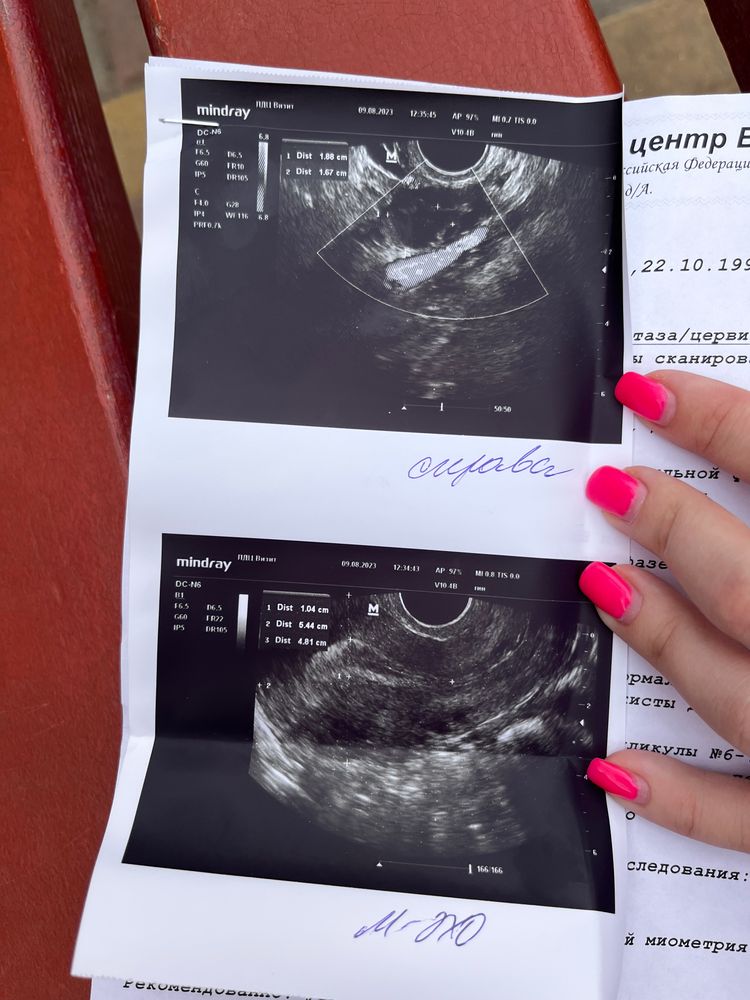

Фолликулометрия 17дц. Подскажите!

Здравствуйте! Жидкость означает что овуляция прям вот-вот только случилась. Эндометрий всегда уменьшается, компактизуется после овуляции, так что всё отлично 👍 10мм это прям супер! И по дням вы хорошо попали) Кисты на ШМ очень частая история и многие врачи даже не пишут это в заключении, так как это ничему не мешает и никак вам не угрожает!)

Nelly, отлично 😁. блин, а то что написано эндометрий неоднородный, хотя на 10дц и на 17дц был однородный, четкий, ровный, трехслойный.